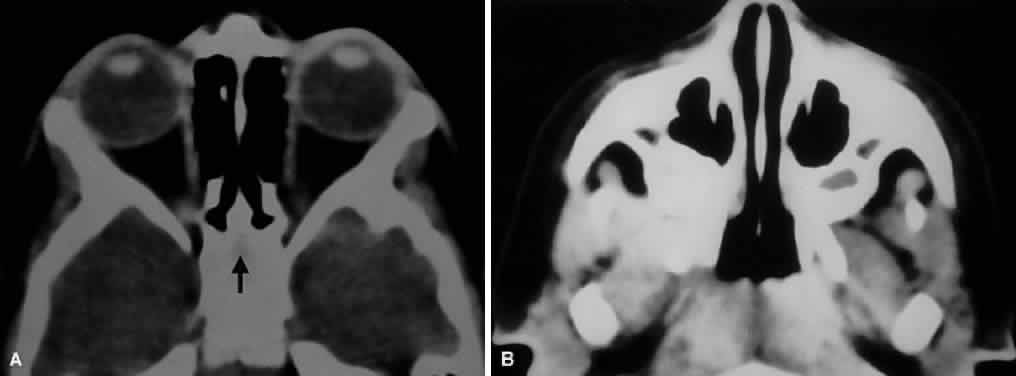

A clear understanding of the relation of the bony orbit to the skull and the midface allows for a logical interpretation of the clinical and radiographic patterns of orbital disease. The bones of the face may be considered to hang from the skull, with attachments at the frontozygomatic and frontoethmoidal sutures, as well as the sphenoid bone. Craniofacial dysjunction occurs in these areas in Le Forte III fractures, and the sites of craniofacial articulation are also the basis for the Le Forte III osteotomies used for facial reconstruction in patients with craniofacial synostoses. The complex shape of the sphenoid wing provides for an intimate communication between the CS, the orbital apex, and the pterygopalatine fossa. Radiographically, the spaces and foramina of the orbital apex may be considered to lie in three tiers (Fig. 8). The CS is found on the same level as the orbital apex, connecting directly with it via the superior orbital fissure (SOF) to form the middle tier. The inferior tier is formed by the inferior orbital fissure (IOF), which provides direct communication between the orbital apex and the pterygopalatine fossa, a vertically oriented space directly behind the maxillary sinus. Finally, the optic canal has no direct communication with any of the aforementioned spaces and should be considered to lie above the SOF and CS, exiting the orbit in a superomedial course through the body of the sphenoid as the superior tier.26 Orbital apical lesions can therefore gain ready access to the CS and pterygopalatine fossa (Fig. 9). Spread into the cranial vault through the optic canal is usually limited to lesions of the optic nerve (glioma) or nerve sheath (meningioma). PARANASAL SINUSES The orbit is surrounded on three sides by the paranasal sinuses (see Fig. 5). The ethmoid sinus runs along the medial orbital wall and is divided into anterior, middle, and posterior air cells by a highly variable system of septa. It is the only sinus to be fully pneumatized at birth. The thin lamina papyracea of the medial orbital wall and the vascular foramina for the anterior and posterior ethmoidal arteries provide scant resistance to the extension of infections and tumors from the ethmoidal sinus to the orbit, even in the adult (Fig. 10). The maxillary sinus borders the orbital floor and is fully pneumatized by 2 to 4 years of age. Unlike the ethmoid sinus, it contains no supporting septa. Although the lamina papyracea is the thinnest of the orbital walls, the network of septations within the ethmoid air cells acts as a supporting scaffolding to the medial orbital wall, much the same way that corrugations strengthen cardboard. Thus, the orbital floor, although not the thinnest wall, is the most frequently fractured, having no underlying support within the maxillary sinus. The posterior wall of the maxillary sinus forms the anterior wall of the pterygopalatine fossa. Frontal sinus pneumatization is highly variable and may continue into the teenage years. Because it drains into the anterior ethmoid air cells, the frontal sinus is often concurrently involved in ethmoid sinus pathology. Supraorbital sinuses are defined as lateral extensions of the ethmoid sinus and span the orbital roof for variable lengths. On occasion, pneumatization to the level of the frontozygomatic suture may occur. Finally, the sphenoid sinus abuts the orbital apex and is the last to pneumatize. Because of the proximity of the optic canal and CS (see Fig. 8), any sphenoid sinus pathology may manifest as a parasellar syndrome (discussed later). Pneumatization of the sphenoid sinus may extend into the anterior clinoid process, a variation of normal anatomy often encountered in orbital imaging studies. FORAMINA AT THE ORBITAL APEX The orbit is generally found to contain nine openings (Table 5). Only the optic foramen, SOF, and IOF will be discussed in detail (see Fig. 8). The optic foramen is located in the medial wall of the orbit in the body and lesser wing of the sphenoid bone. The optic canal is 4 to 10 mm long and 6.5 mm wide. On imaging studies, a 1-mm difference between canal diameters is considered clinically significant. The optic canal transmits the optic nerve, the ophthalmic artery, and the sympathetic innervation to the orbit. Note that sympathetic nerves also travel with the nasociliary nerve via the SOF.